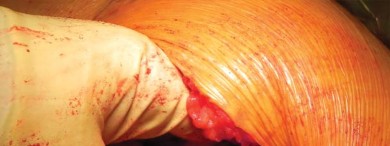

يتم عمل شق مائل من الخلف القريب إلى الأمام البعيد، يتمركز فوق طرف المدور الكبير، ويبلغ طوله حوالي 10-12 سم للرجل متوسط الوزن (70 كجم). يتم تقليل تشريح تحت الجلد لتحديد اللفافة الأساسية إلى الحد الأدنى لمنع تكوين مساحة ميتة.

إدارة الأنسجة الرخوة وخلع رأس الفخذ

تُشق اللفافة العريضة والألياف الأمامية للعضلة الألوية الكبرى التي تتصل باللفافة العريضة قريبًا باستخدام الكي الكهربائي بما يتماشى مع شق الجلد. يتم إزاحة الجراب المدوري خلفيًا للمساعدة في رؤية العضلة الألوية الوسطى والعضلة المتسعة الجانبية. يتم رفع الجزء الأمامي من العضلة الألوية الوسطى عن المدور الكبير باستخدام الكي الكهربائي، ثم يتم تشريحه بشكل غير حاد بما يتماشى مع أليافه بزاوية 45 درجة أمامية-قريبة عند تقاطع الثلثين الأوسط والأمامي للعضلة. يقتصر التشريح على أقل من 3-4 سم باتجاه الرأس من طرف المدور الكبير لتجنب إصابة العصب الألوي العلوي. في غلاف مستمر مع العضلة الألوية الوسطى، يتم رفع الجزء الأمامي من العضلة المتسعة الجانبية عن حافة العضلة المتسعة ويتم شقه بعيدًا بين ثلثيه الأوسط والأمامي. يتم وضع مبعد هومان غير حاد في شق العضلة الألوية الوسطى لسحب الألياف الخلفية وكشف طبقة من الدهون بين المستويات الألوية. تُشق الكبسولة خلف العضلة الألوية الصغرى وعلى طول الجانب العلوي من عنق الفخذ. يقوم المساعد بتباعد وثني وتدوير الطرف خارجيًا لخلع رأس الفخذ.